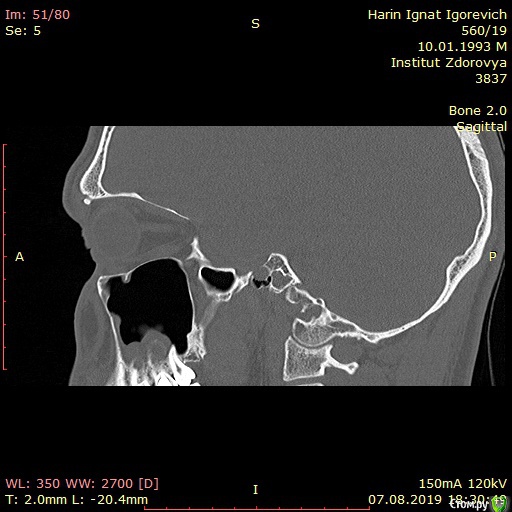

Игнат46 Опубликовано 9 декабря, 2019 Поделиться Опубликовано 9 декабря, 2019 Город Москва. Одонтогенные кисты у корней 16,17 зубов Добрый день. Ищу клинику и специалиста для лечения кист.Сделал КТ пазух носа, и обнаружились кисты на корнях двух зубов. Ничего не беспокоило, прошел месяц, а сейчас уже второй день чувствую боль при нажатии на десну в этой области и некоторую опухлость . Ссылка на комментарий